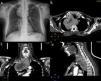

Caso 1Una mujer de 61 años fue enviada a nuestro centro por un hipertiroidismo subclínico de 12 meses de evolución. A la paciente se le había practicado una tiroidectomía subtotal previa a causa de un bocio multinodular 7 años antes en otro centro. Se detectó un hipertiroidismo en las pruebas funcionales tiroideas. La tomografía computarizada (TC) mostró un tiroides cervical retrotraqueal en continuidad con la masa mediastínica posterior que se extendía más allá del cayado aórtico y la vena ácigos (fig. 1). El bocio producía un desplazamiento de la tráquea y del esófago hacia el lado izquierdo terminando a la altura de la aurícula derecha, por debajo de la carina traqueal. La exploración laringológica descartó una parálisis del nervio recurrente. La espirometría mostró una capacidad vital forzada (FVC) de 3,62 l (109%) y un volumen espiratorio forzado en el primer segundo (FEV1) de 2,88 l (114%).

Caso 2Una mujer de 64 años fue ingresada en nuestro centro con un BE de 6 meses de evolución. El BE se identificó durante una evaluación rutinaria por una fibrilación auricular. Las pruebas de función tiroidea fueron compatibles con un estado eutiroideo. La TC mostró una masa lobulada en la glándula tiroides adyacente al polo inferior del lóbulo derecho (fig. 2). Se observó que la masa se extendía retrotraquealmente hasta 3cm por debajo de la carina traqueal. La espirometría mostró una FVC de 2,63 l (60%) y un FEV1 de 1,92 l (61%).